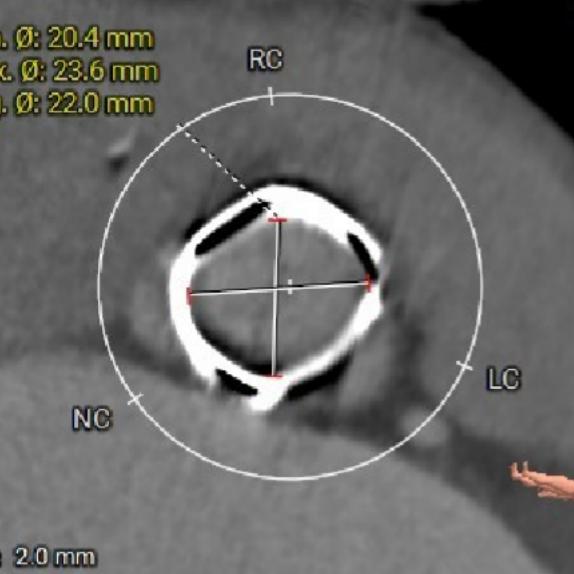

术前CT评估-TAVI viv

瓣架高度

瓣上2mm